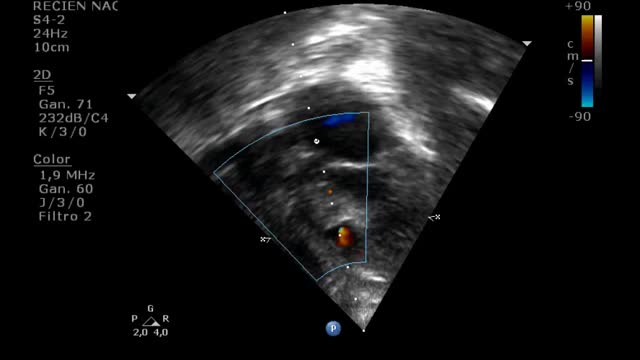

We present a case of a 6-month-old male infant who underwent intracardiac repair for Tetralogy of Fallot (TOF). He was operated by total repair approach with pulmonary valve preservation and after surgery he was shifted to Intensive Unit Care. Informed consents for surgery and publication were provided in accordance with national legislation. In an ultrasound routine check-up during the immediate postsurgical period, a constant pulsatile flow in the interventricular septum which reached the right ventricular outflow tract was detected, compatible with a coronary artery fistula (CAF) from the left coronary artery to the right ventricle (RV) (Fig. 1, Video 1.)

We performed an enzimatic curve, an ultrasound image and an ultrasound continuous doppler (Fig. 2) and there were not any evidence of myocardial ischemia. The patient remained asypmtomatic during the hospital stay and progressed correctly. Spontaneous closure of the CAF occurred one month after the initial diagnosis.